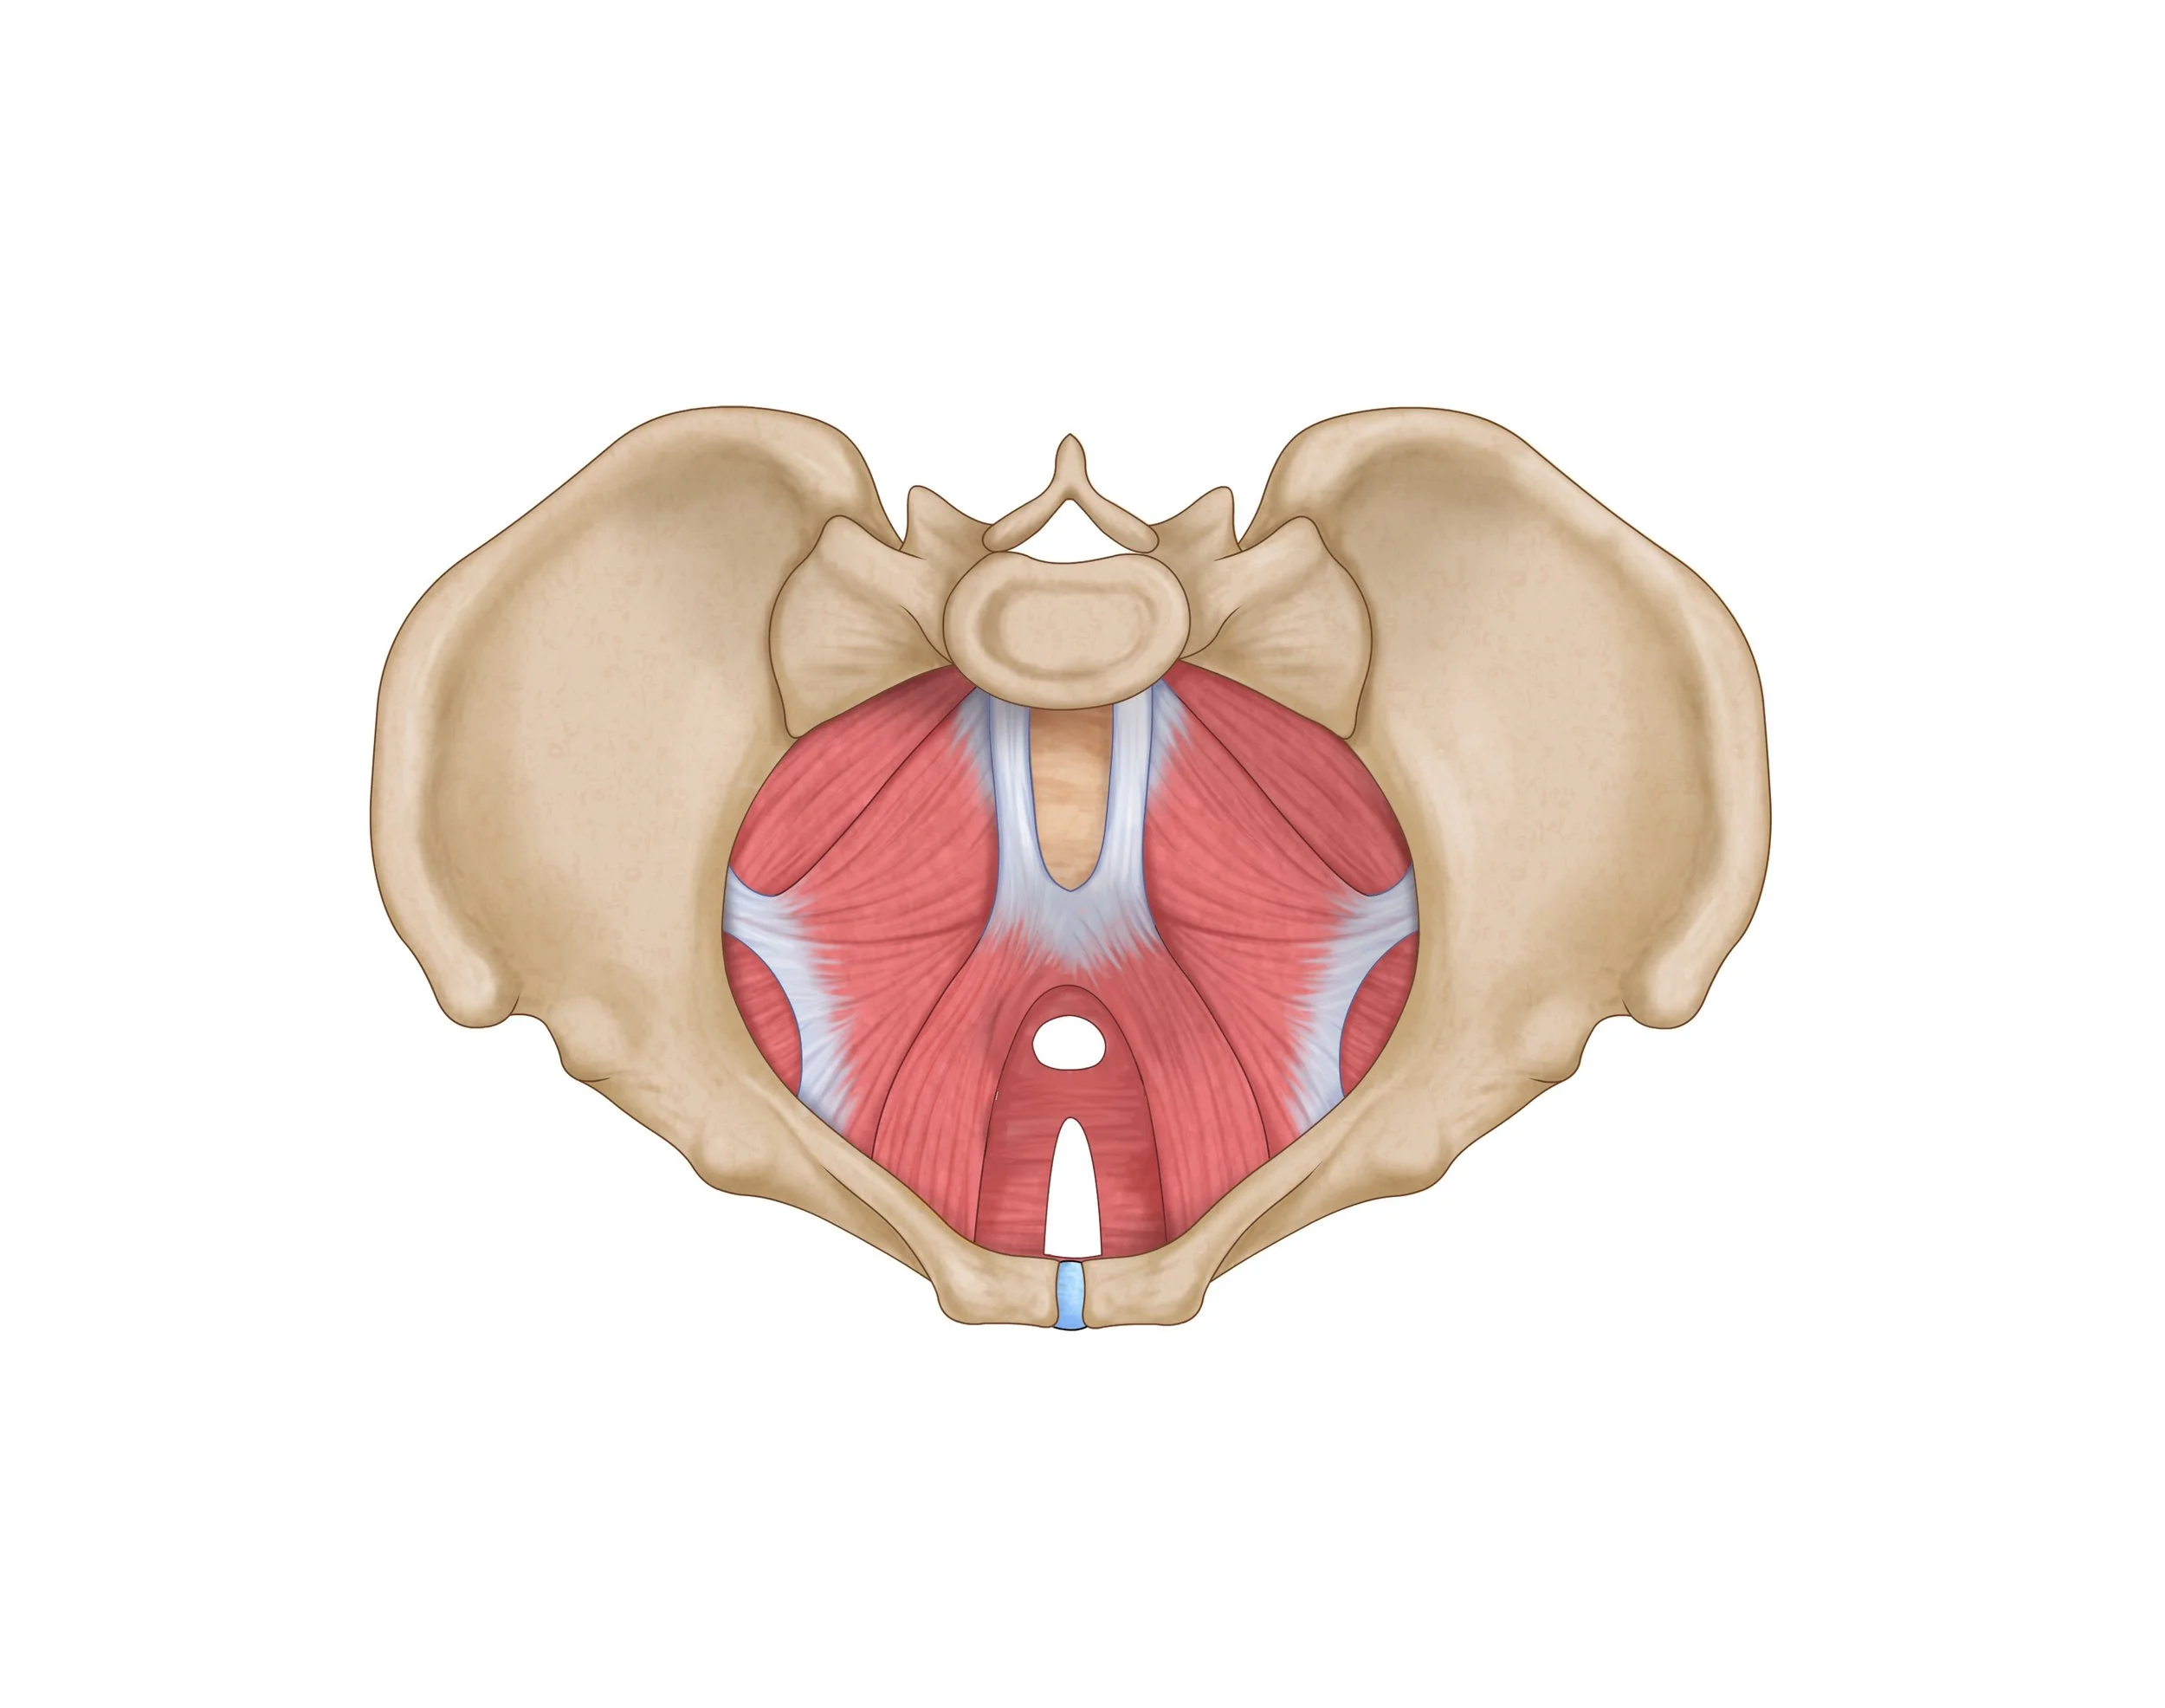

The Pelvic Floor An anatomical review

The pelvic floor consists of several layers of muscle contained within the pelvis that are designed to support the abdominal and pelvic organs, allow for proper bowel and bladder voiding, sexual activity, and child birth. Just like any other muscle in the body, we can experience issues from these muscles being too weak, too short, too long, overactive, or underactive. However, pelvic floor muscles can be rehabbed similarly to our other muscles as well. For example, if I strain a muscle in my leg, I’m going to work on getting the injured muscle and the surrounding area stronger, improve muscle length, and activate at the appropriate times. The pelvic floor muscles function in the same way as other muscles in our body, and need similar attention if there is pain or dysfunction.

view from above